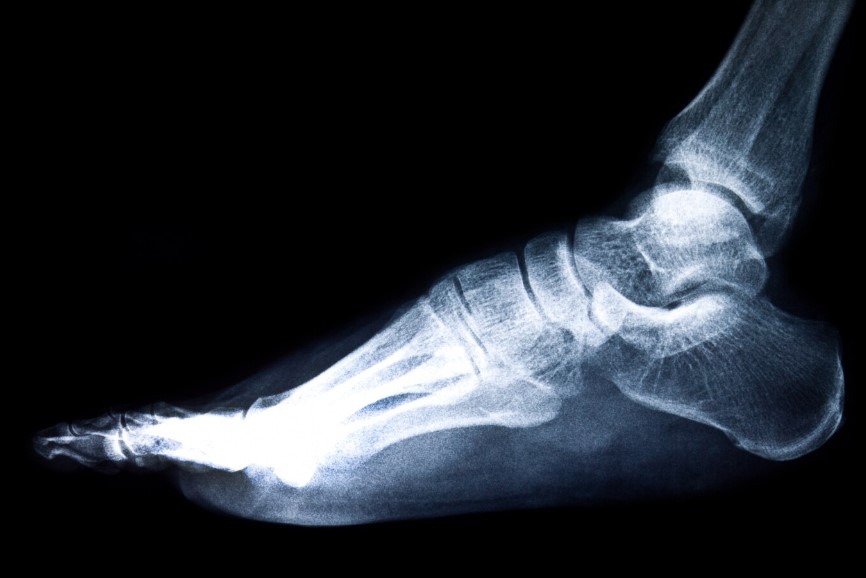

Рентген голеностопного сустава

Востребованным диагностическим методом при травмах и заболеваниях ног в течение многих десятилетий остается рентген голеностопного сустава.

Исследование выполняется при помощи рентгеновского излучения, которое пропускают через нижнюю конечность.

В результате на чувствительном экране появляется изображение костей, формирующих сустав и стопу.

По характеру деформаций костных структур и другим признакам, отображенным на снимках, определяется диагноз и назначается оптимальный вид лечения.

• Что показывает рентген голеностопного сустава?

На снимке опытный диагност легко различает:

• трещины или переломы костей;

• вывихи сустава;

• наличие новообразований;

• признаки воспалительных процессов;

• нарушения костной структуры;

• кальциноз сосудов нижней конечности;

• некротический процесс мягких тканей;

• наличие пяточной шпоры;

• врожденные или приобретенные деформации костей.